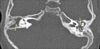

The patient was admitted to the hospital. A CT scan of the inner ear and mastoids revealed bilateral opacification of the mastoid air cells with mild erosion of the tympanic portion of the facial canal on the left side (Figure). He underwent bilateral myringotomy with pressure-equalizing tube placement and received intravenous ceftriaxone and dexamethasone as well as ciprofloxacin/dexamethasone otic suspension. The patient was discharged after 3 days with prescriptions for oral amoxicillin/potassium clavulanate and ciprofloxacin/dexamethasone otic suspension. He recovered uneventfully.